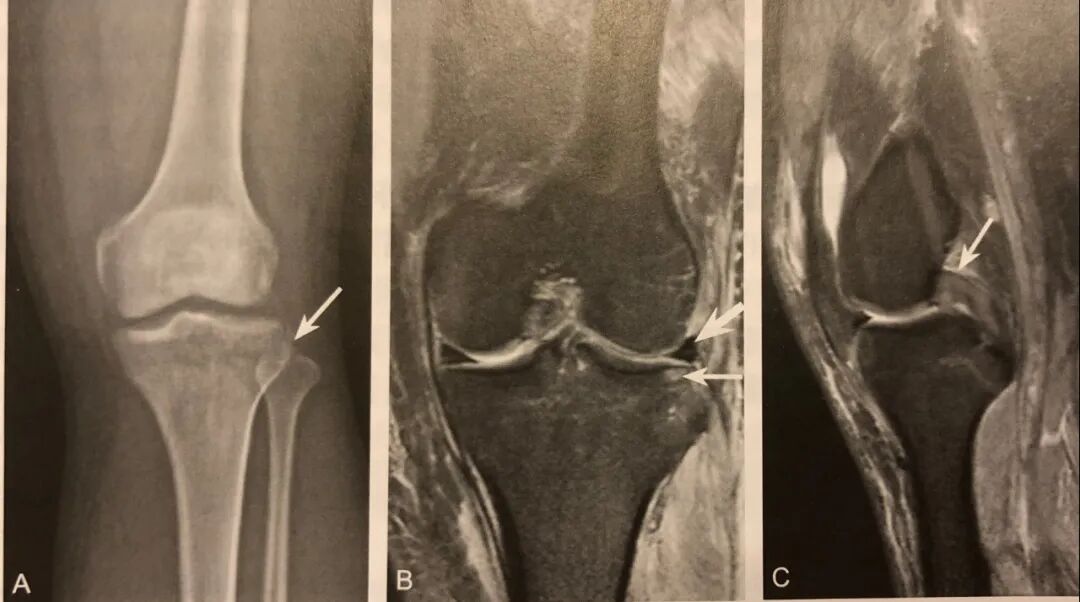

1. 腓骨小头撕脱性骨折的直接征象,弓形复合体和后外侧角损伤的间接征象;

2. 在膝关节X线前后位或 CT、MRI 冠状位观察,表现为近端腓骨小头或腓骨茎突撕脱性骨折,碎骨片呈弓形;

3. X 线片或 CT 观察到弓形征后,须行 MRI 检查,观察弓形复合体及后外侧角的完整性;

4. 少数后外侧角损伤合并腓总神经及胭动静脉损伤。